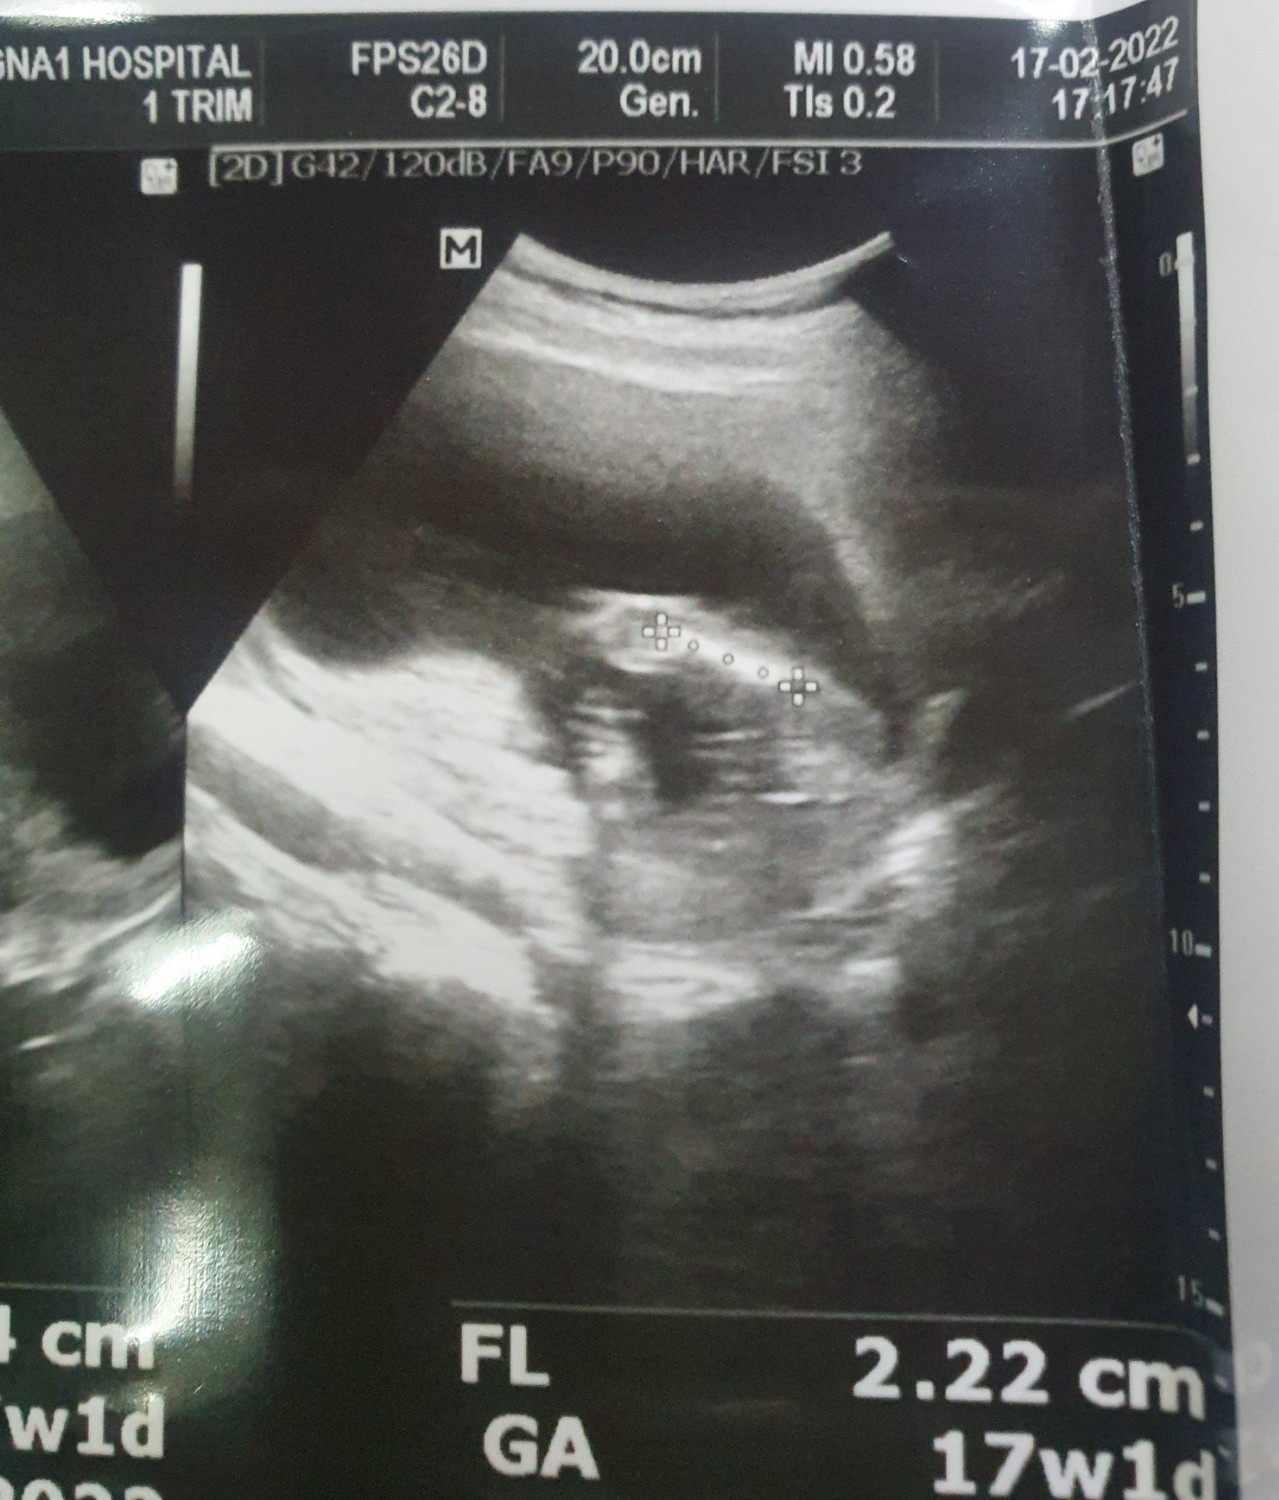

ช่วยดูเพศลูกให้หน่อย